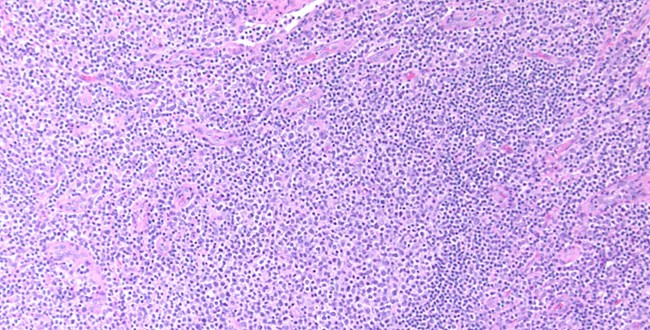

Linfoma folicular plasmocitoide

Autores: Dra. Dana Kohan, Dr. Boris Elsner, Centro de Patología, CABA. Reseña: Mujer de 51 años con múltiples adenopatías. Se estudia ganglio inguinal, con arquitectura folicular, presentando ...